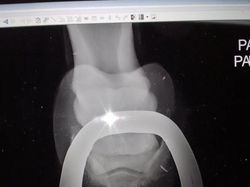

Penasaran bagimana hasil sinar X kaki kuda? begini hasilnya. (Foto: Brightside)